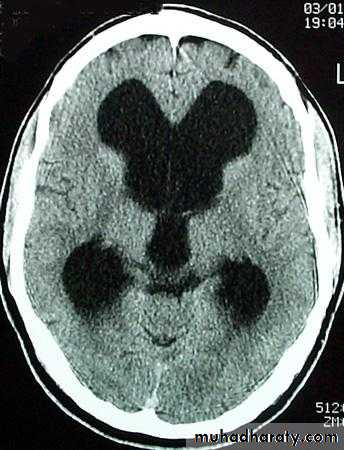

Obstructive ( non – communicating )

Craniophyrengioma

Medulloblastoma

Ependymoma

Aquiduct stenosis , comments cause of obstruction being congenital in nature .

Non –obstructive ( communicating )

No obstruction of the ventricular pathway , but the absorption of the csf at the level of arachnoids' granulation is occluded secondary to lodge by blood clot or inflammatory cell or infection post meningitis most commonly to occur post SAH .